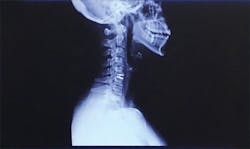

Seeing the scar on my neck, resulting from the subsequent cervical disk replacement surgery, patients were more willing to lie back farther and turn toward me when I asked. I frequently ask myself if surgery could have been avoided if I had advocated for myself and required my patients to accommodate me. If I had invested in my loupes and my saddle stool earlier, could that have helped?

A scar on the author’s neck from cervical disk replacement surgery